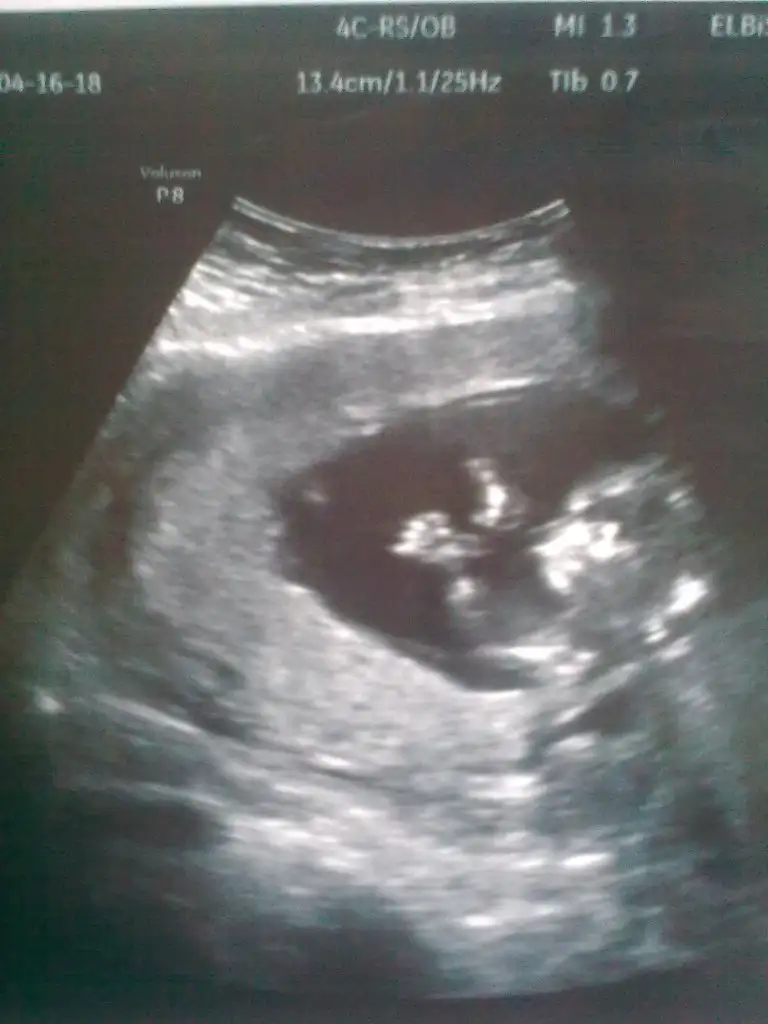

Erkek benceeYA KIZLAR BANA NEDEN YORUM YAPMIYORSUNUZ CATLIYORUM BURDA MERAKDANN :) daha ufak ama banada biseler soyleyin nolurrrrr![]()

Bence erkekYA KIZLAR BANA NEDEN YORUM YAPMIYORSUNUZ CATLIYORUM BURDA MERAKDANN :) daha ufak ama banada biseler soyleyin nolurrrrr![]()

Ay hadi insallah:)Bence erkek

Banada oyle geliyo bi an once ogrenmek istoyorummmm:)Erkek bencee

Buyuj ihtimak kizz...kızlar 14 haftalık hamileyim dr.bişey demedi cinsiyetine lütfen yorumlarmısınız....merakla bekliyoruz......